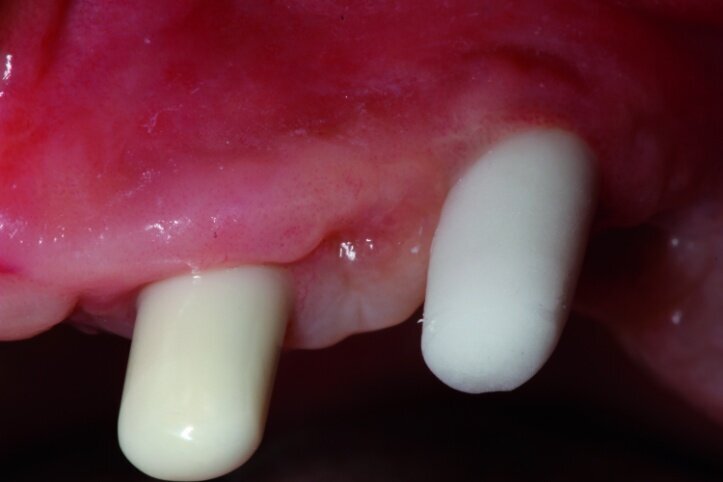

Each treatment should start with a well-prepared plan. For most patients appearance after treatment will always be very important that is why an intraoral analysis must be made in order to assess the static structure of the mouth, as well as an analysis of the lips’ dynamics along with teeth exposure during speaking and smiling (Figs. 1 & 2).

We analysed the aesthetic aspects in a way that enables us to reach an optimal balance between white (teeth) and pink (gums) aesthetics. Of course, in toothless patients, one should take note of the fact that teeth setup as well as reconstruction of atrophied tissues will constitute a support for the lips. Such an analysis may be made on the basis of a restoration that the patient uses. In this case, first sanitation of the maxilla had to be performed, next a temporary acrylic prosthesis was made.

In the next phase, implants were inserted. In compliance with the results of the CBCT study, a sinus lift procedure was performed with a simultaneous implantation in the region of lateral teeth. Eight Ankylos implants were introduced, raising both maxillary sinuses at the same time. After six weeks, the implant exposure procedure was performed. Because of the fact that implants were partially anchored into the bone at the lateral section, partially within the augmentation material while primary stability was achieved, we decided to expose implants at lateral sections without occlusal load so as to perform the so-called bone training with a view to improving the condition of the bone being regenerated. An impression was taken (Figs. 7 & 8) for the positional model and for the preparation of the temporary prosthesis based on telescopes.